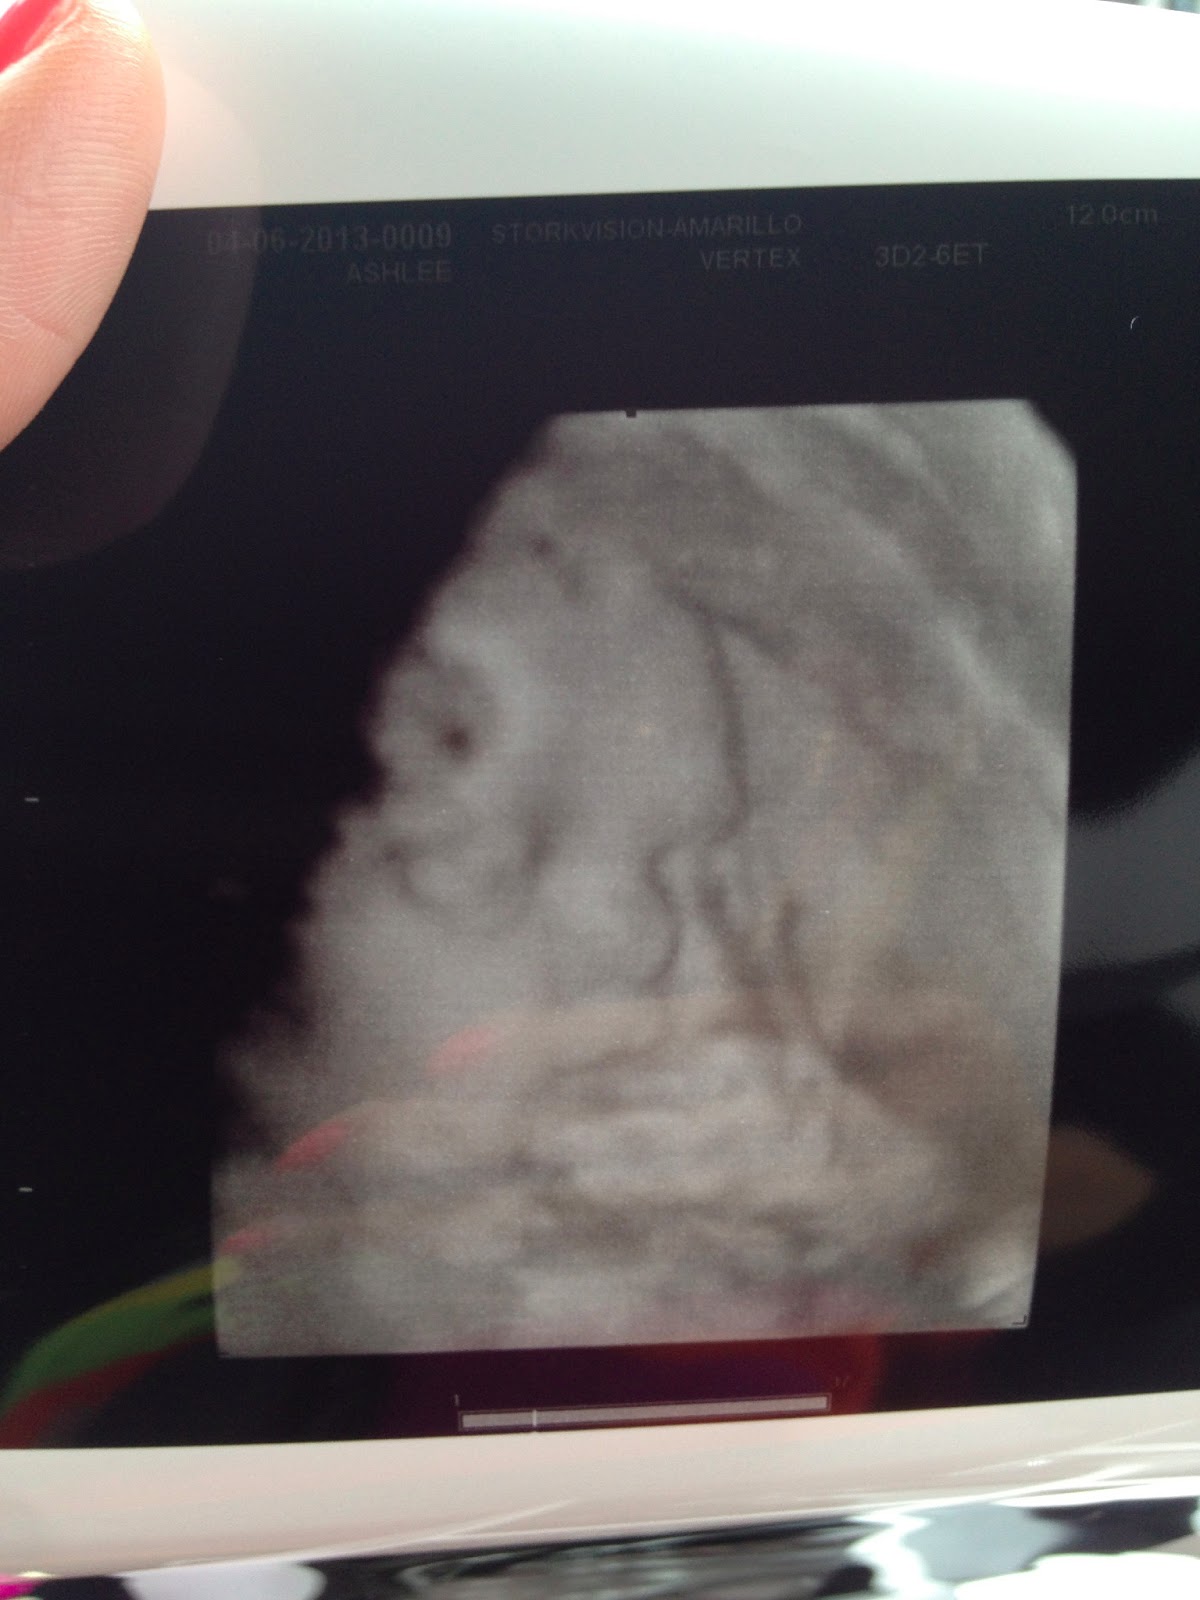

- Best Moment of the Week: Seeing Little Miss in a 3d/4d sonogram, getting her bedding in…and I LOVE IT….and having our first shower given by my “school family”. It’s been a busy, fun and exhausting week! 🙂

Here are some pictures from the sonogram!30 weeks!